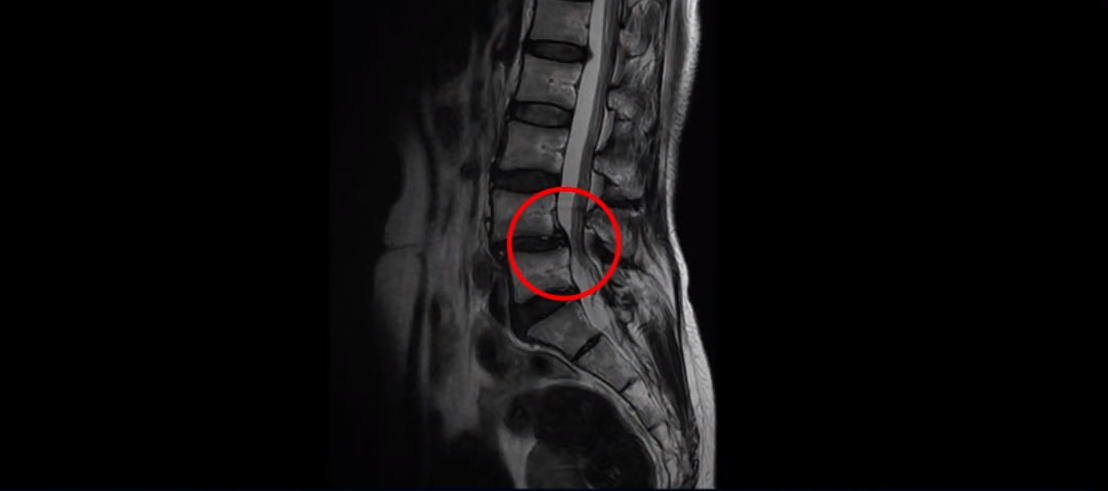

제가 이 환자분의 MRI를 보면서 먼저 설명 드리고 그 이후에 이 환자분의 이야기를 직접 들어 보시겠습니다.

이 환자분은 아주 심하게 넘어지면서 엉덩이 근육이 파열되고 고관절에 미세 골절이 발생한 분입니다.

또 한 가지 추가로 말씀드릴 건 이 환자분은 전방전위증으로 인한 만성적인 허리통증을 수년간 겪고 계신 분이었습니다.